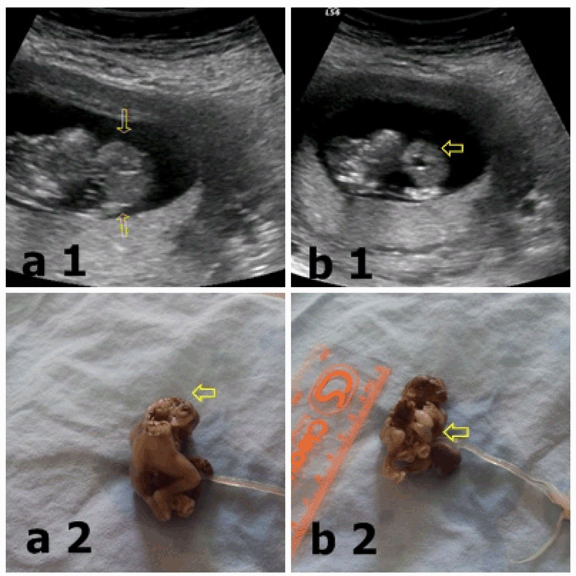

A 26-year-old (G4P1) woman was admitted to our hospital at her 12th week of gestation. In the routine ultrasound examination for first-trimester screening, crown rump length (CRL) was 40 mm in diameter, compatible with the single live fetus of 10 weeks 6 days. The fetal calvarial bone was deformed (exencephaly). (Figure 1a1) The view of herniated organs out of the abdominal wall defect and the defects in the lower end of the sternum was compatible with omphalocele and ectopia cordis. (Figure 1b1) Fetal spine was deformed and short. With these available ultrasonographic findings the diagnosis of Pentalogy of Cantrell was established and the pregnancy was terminated with the consent of mother and father. By the postmortem examination fetal omphalocele, (Figure 1b2) ectopia cordis and diaphragmatic hernia was detected. In addition to these findings, we observed an exencephaly continuing with spinal dysraphism as additional anomaly (craniorachischisis). (Figure 1a2) Fetal spine was deformed and short.

Figure 1: (a1) ultrasonografic view of exencephaly, (a2) exencephaly, (b1) ultrasonografic view of omphalocel and ectopia cordis and (b2) omphalocel.